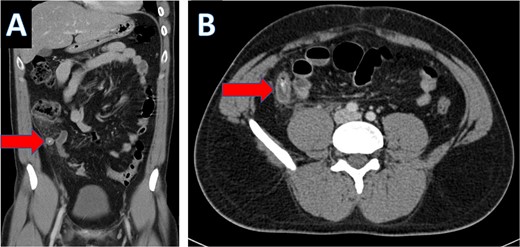

An IV contrast-enhanced CT scan of the abdomen and pelvis revealed an 8-mm proximal to mid-ureteral obstructive stone on the right side (Fig. 1), causing severe hydronephrosis of the right kidney and proximal hydroureter (Fig. 2).

CT scan showing right ureteral calculus (A: coronal; B: axial).